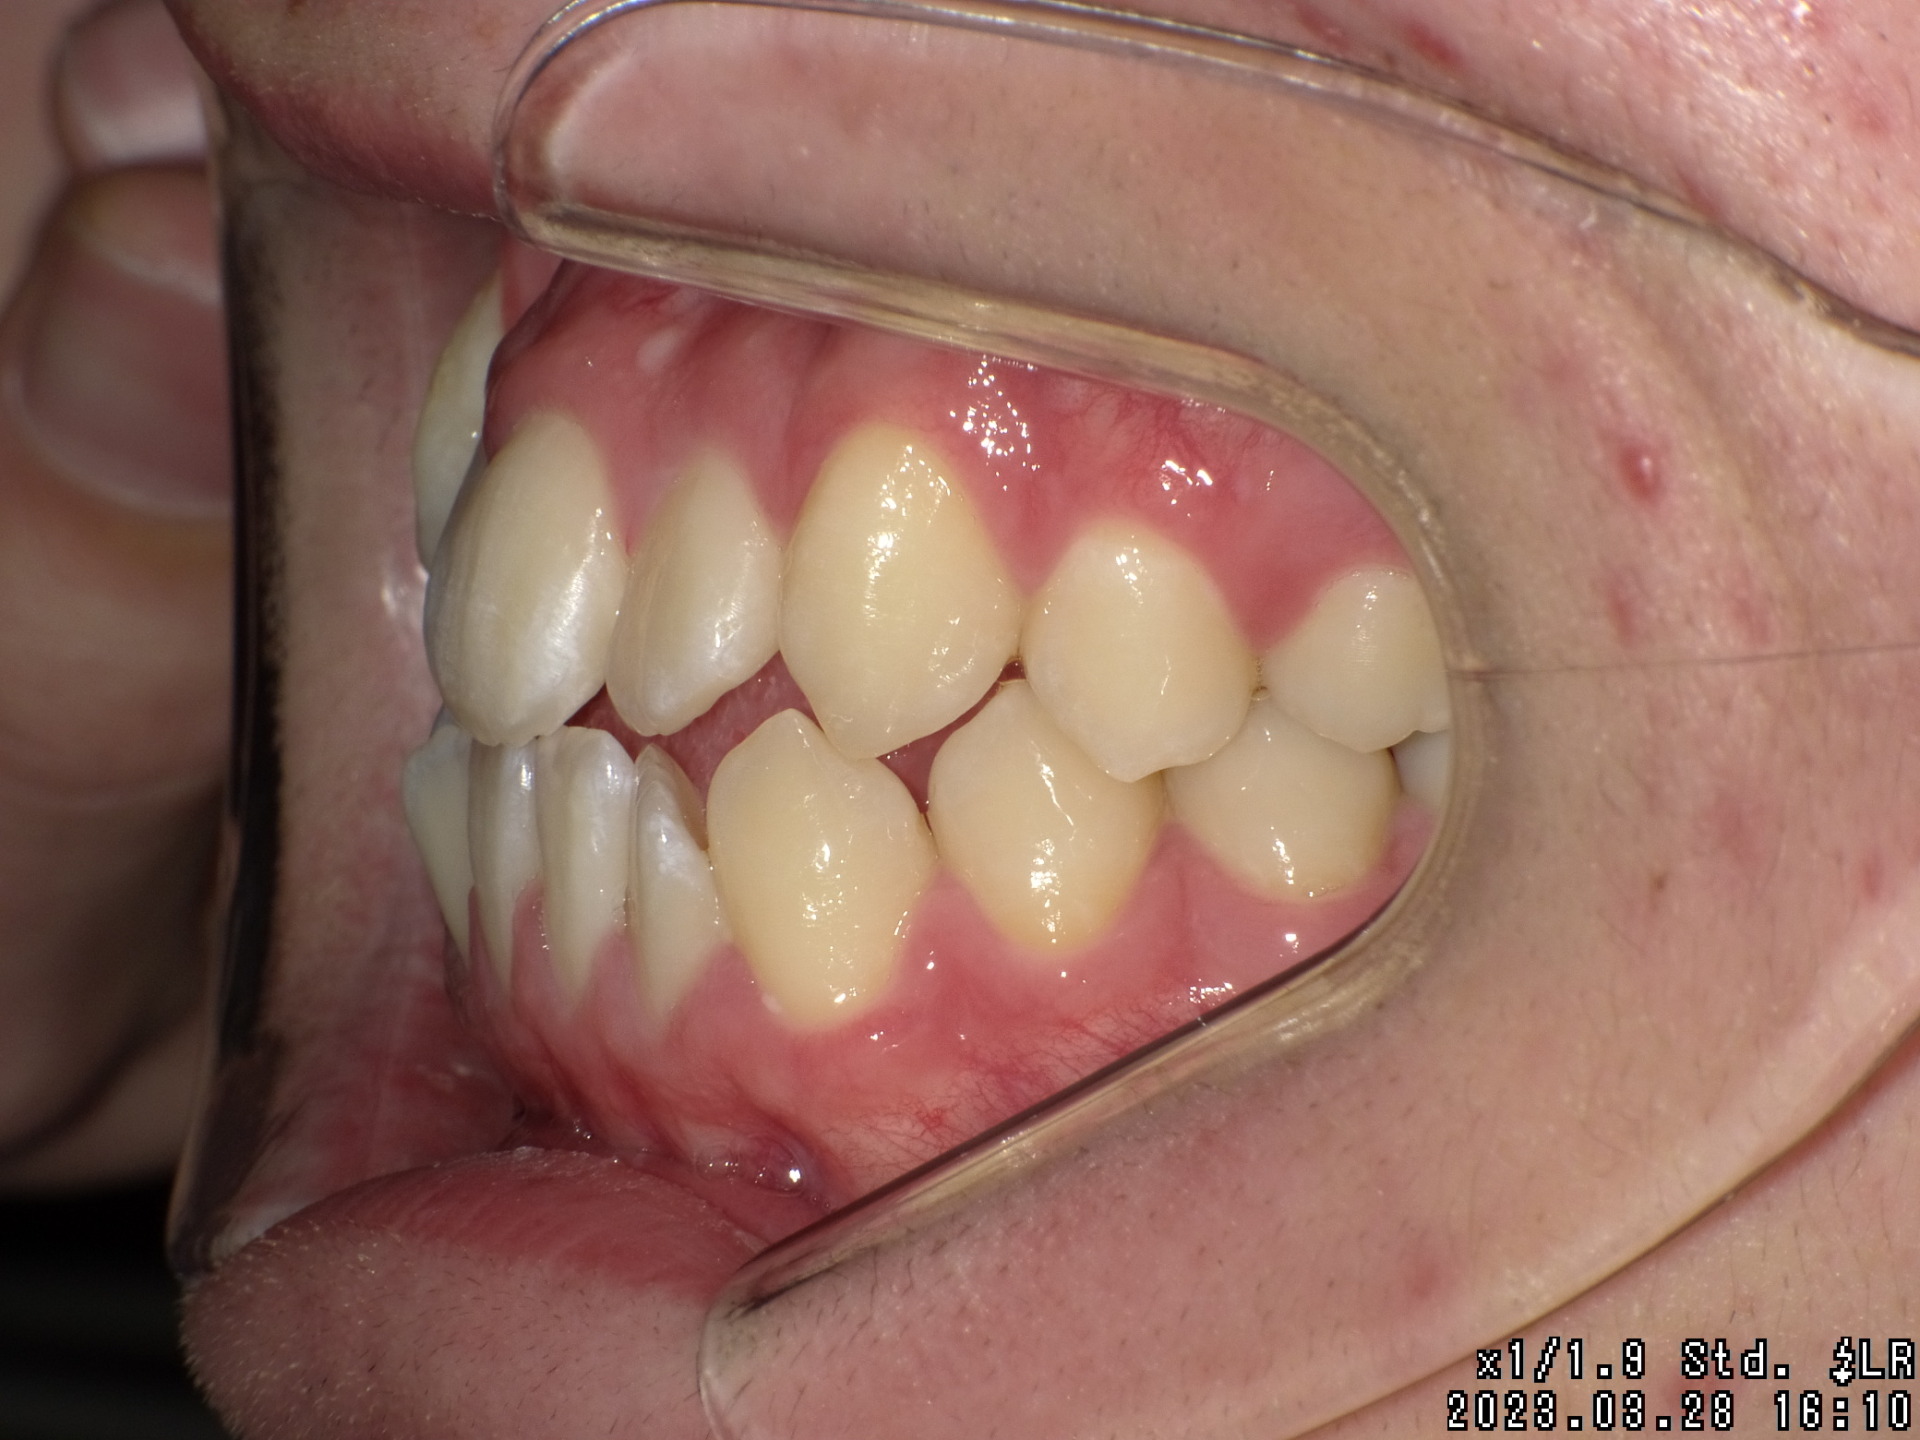

Before

| 症状 | 右上八重歯 上顎正中の著しいずれ |